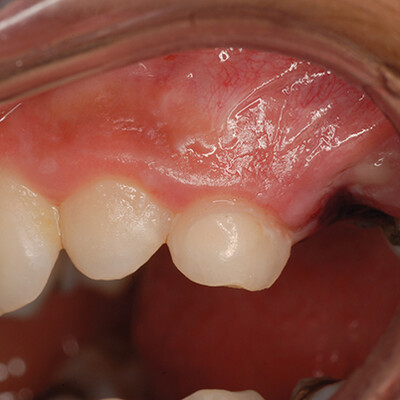

Случай 1: EQUIA Forte на молочном клыке

6-летний пациент с плохим сотрудничеством обратился с лицевым кариесом на зубе № H (рис. 1). После удаления кариеса на участок был нанесен кондиционер поверхности (Cavity Conditioner, GC America Inc.) на 10 секунд, промыт в течение 10 секунд, а затем высушен, но не высушен. EQUIA Forte был установлен, ему дали затвердеть, затем нанесли EQUIA Forte® Coat и светоотвердили (Рисунок 2).

Через 1 год (рис. 3) реставрация держалась хорошо, но цвет не совпадал.